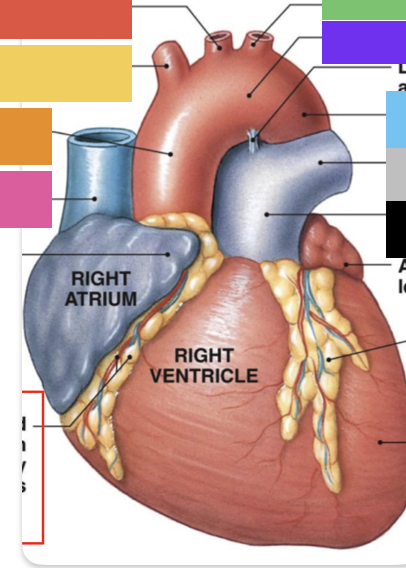

light purple

base

purple

apex

grey

right atrium

pink

right auricle

green

left atrium

green

left auricle

blue

right ventricle

orange

left ventricle

green

coronary (atrioventricular) sulcus

pink

interatrial septum

dark blue

interventricular septum

green

anterior interventricular sulcus

green

posterior interventricular sulcus

orange

aortic valve

yellow

pulmonary valve

red

tricuspid valve (right AV)

purple

bicuspid valve (left AV)

yellow

chordae tendineae

orange

papillary m.

blue

trabeculae carneae - only in ventricles

red

pectinate m. - only in R atrium

pink

fossa ovalis

grey

opening of coronary sinus

green

ligamentum arteriosum

green

fibrous pericardium

pink

visceral pericardium (connective tissue) / epicardium (muscle)

purple

myocardium

grey

endocardium

pink

superior vena cava

black arrow

inferior vena cava

black

pulmonary trunk

red

right coronary artery

yellow

posterior interventricular artery

green

left coronary artery

blue

anterior interventricular artery

pink

circumflex artery

coronary sinus